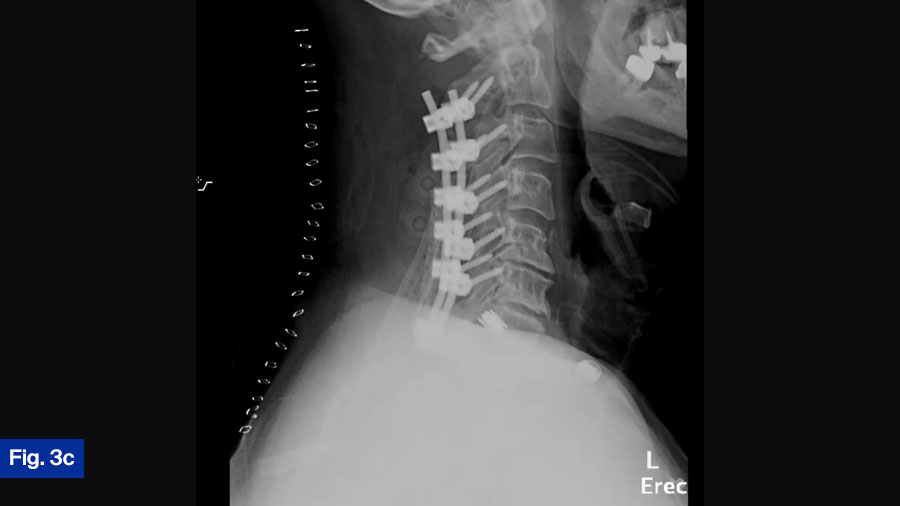

The patient was taken urgently for C2-T1 laminectomy, and C2-T1 posterior cervical fusion (Figure 3c). The patient was covered postoperatively with IV Nafcillin for 2 months, and then transitioned to oral antibiotics. The patient was doing well at final follow-up and was able to ambulate slowly, but without difficulty. Neurologic deficits resolved.